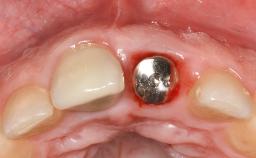

Despite anti-infective surgical treatment, some patients may experience recurrent infection and progressive bone loss requiring additional treatment. Removal of Implant Due to Recurrent Infection describes a conservative approach using an implant retrieval tool without the need for excessive bone removal or use of a trephine.

A 70-year-old female patient was referred by her general dentist to the periodontist for assessment and management of an infection associated with implant 36. The general dentist had noted suppuration on probing during examination.